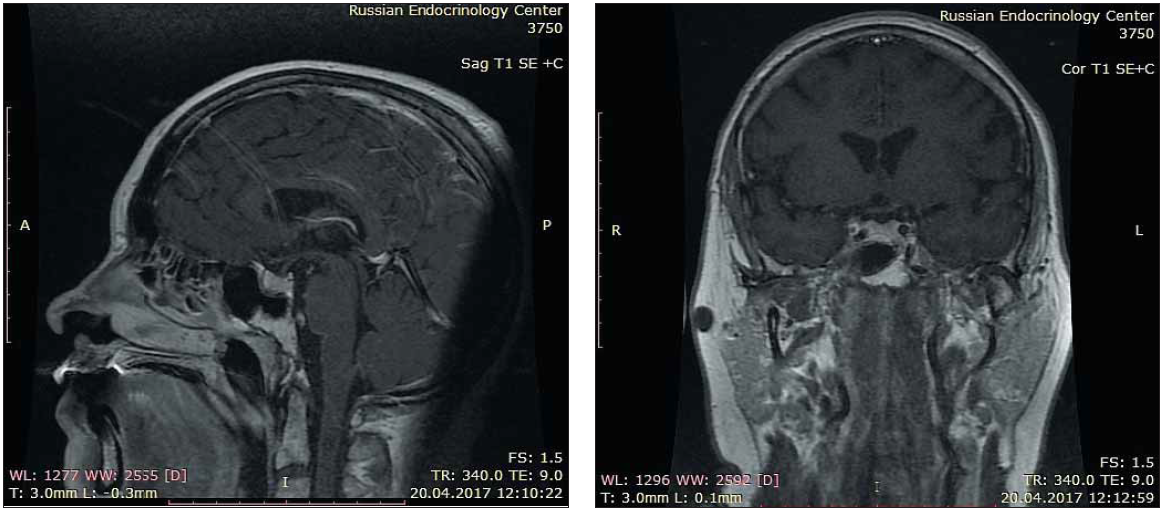

2. Рис. 2. Данные МР-исследования головного мозга до оперативного лечения.

Subject

Type Исследовательские инструменты

View (671KB)

Indexing metadata ▾